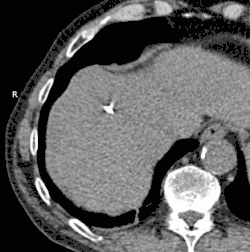

![]() Animated GIF showing cryoablation of mass in right liver lobe using two probes. Time elapsed is approximately 30 minutes. | |